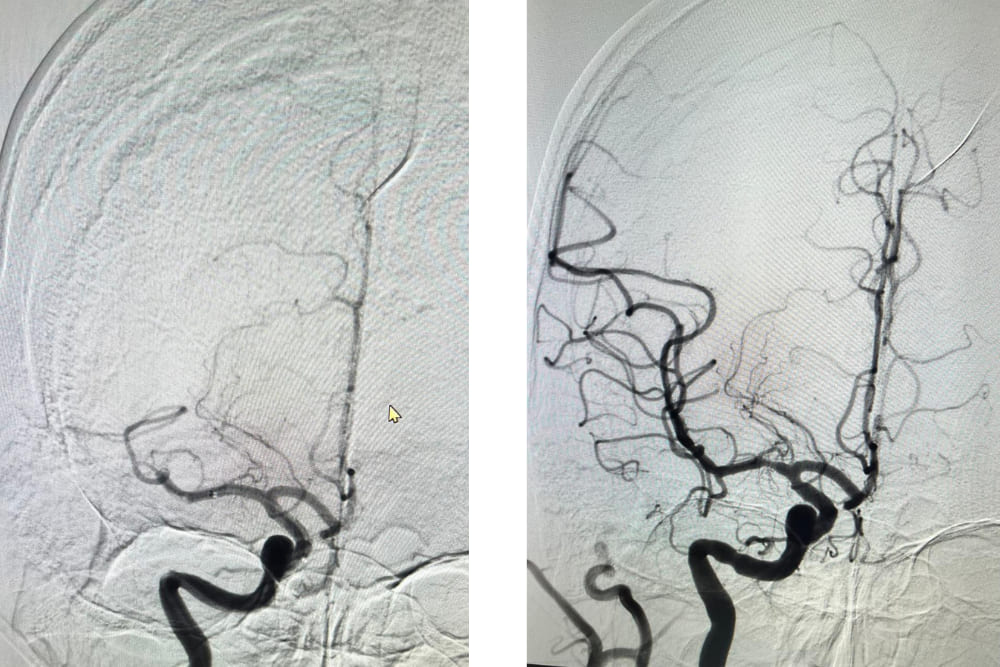

- Procedimientos endovasculares para restaurar el flujo sanguíneo.